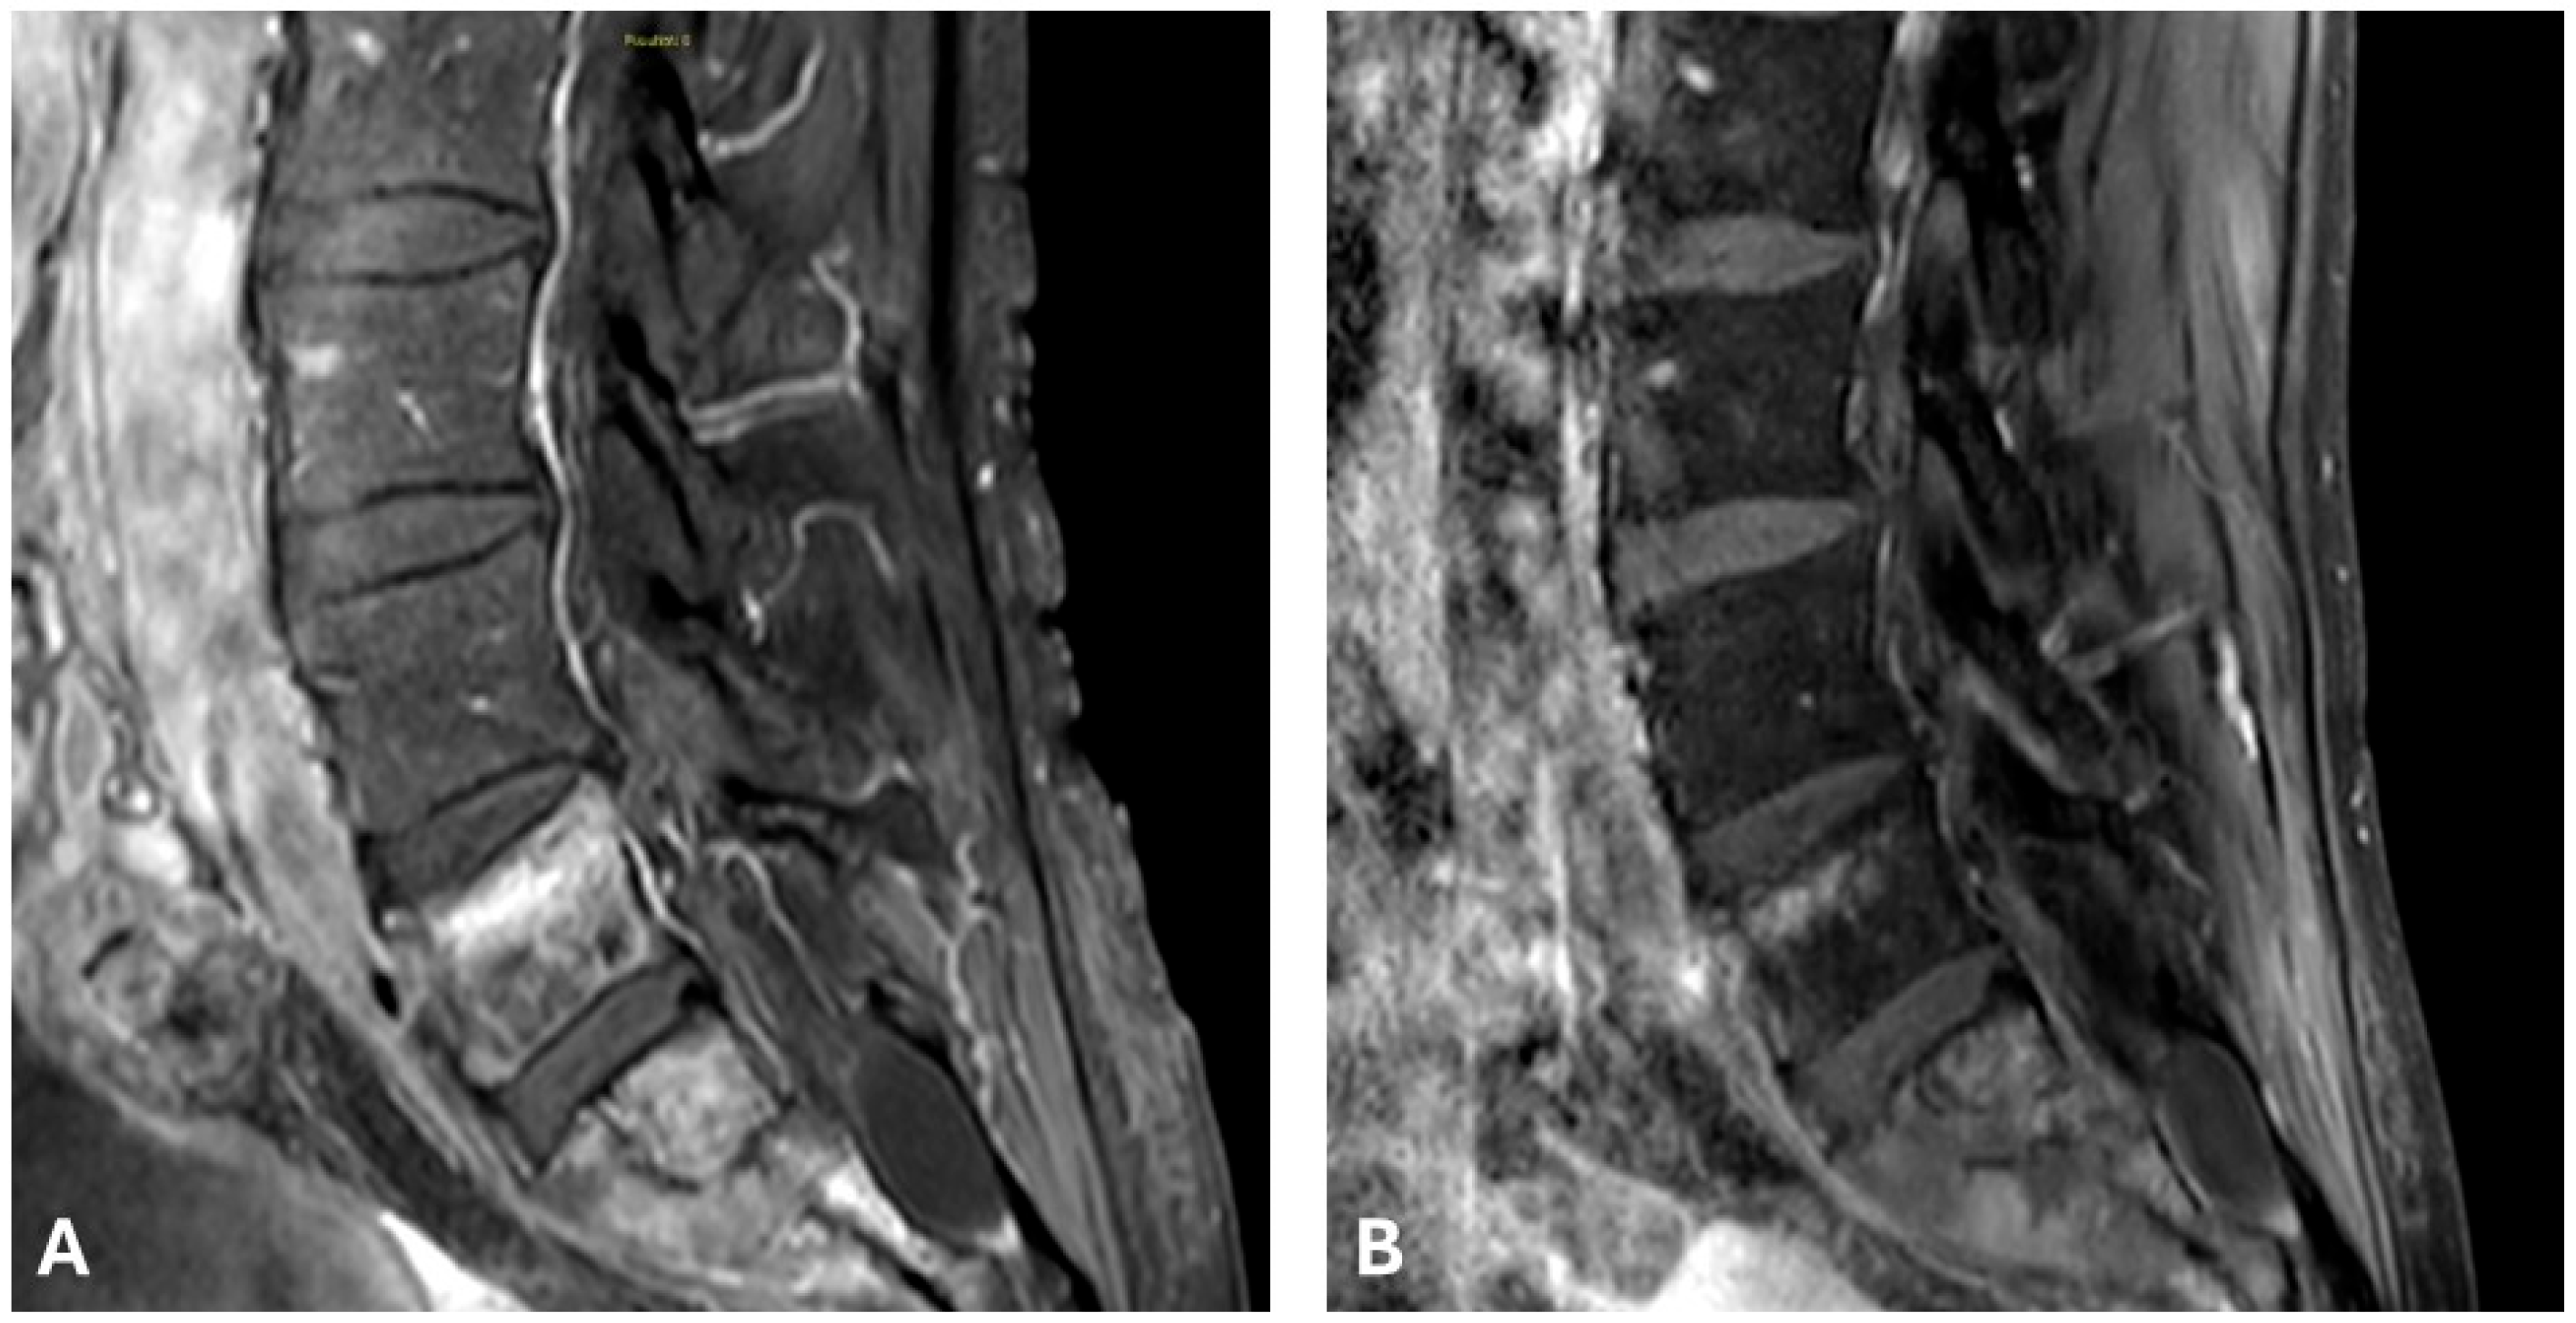

4.1. Spinal Metastases and Spinal Epidural Invasion

- Deschamps, F.; Tselikas, L.; Cazzato, R.L.; Facchini, G.; Granata, V.; Bonnet, B.; D’Alessio, V.; Fusco, R.; Zanasi, A.; de Terlizzi, F.; et al. Electrochemotherapy in Metastatic Epidural Spinal Cord Compression: A Review and Technical Update. Br. J. Radiol. 2025, 98, 828–839. [Google Scholar] [CrossRef] [PubMed]

- Cindrič, H.; Miklavčič, D.; Cornelis, F.H.; Kos, B. Optimization of transpedicular electrode insertion for electroporation-based treatments of vertebral tumors. Cancers 2022, 14, 5412. [Google Scholar] [CrossRef]

- Cindrič, H.; Kos, B.; Tedesco, G.; Cadossi, M.; Gasbarrini, A.; Miklavčič, D. Electrochemotherapy of spinal metastases using transpedicular approach—A numerical feasibility study. Technol. Cancer Res. Treat. 2018, 17, 1–13. [Google Scholar] [CrossRef]

| 2024 | Angelini [18] | 3 | Case Series | Spinal | Transpedicular needle electrodes during surgery + IV bleomycin. | Pain relief and neurologic improvement; stable disease on imaging |